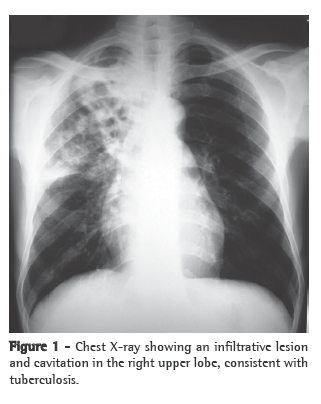

He was acyanotic and presented normal respiration. The chest X-ray (Figure 1) revealed an infiltrative consolidation in the middle and upper lobes of the right lung, suggestive of cavitation. The sputum smear microscopy showed a large number of AFB, suggesting tuberculosis, which was confirmed by culture for Mycobacterium tuberculosis. He was admitted to the isolation ward and started on a quadruple anti-tuberculosis regimen with isoniazid, rifampin, ethambutol and pyrazinamide. Serology was negative for HIV-1 and HIV-2. Urine culture and multiple blood cultures were negative throughout the hospital stay.